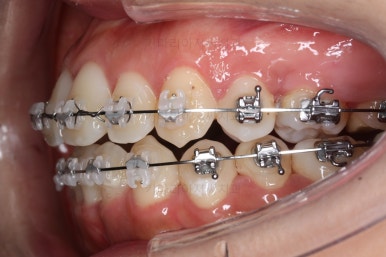

부분적으로 장치 셋팅을 다시 해줬고요.

밀고 당기기를 위해서 미니스크류를 셋팅했고요.

교합과 중앙선 및 디테일을 맞춰 나갑니다.